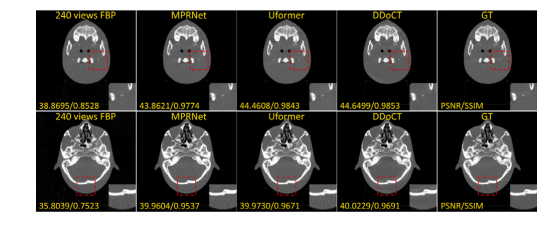

Fig. 6. Comparison of visual (together with quantitative results of PSNR and SSIM)images of the anthropomorphic head phantom dataset, which comprises pairs of CTimages acquired using on-board CBCT scanner with low-dose (80 kV, 100 mA) andhigh-dose (80 kV, 400 mA) settings, respectively. The set range of the display windowis a window level of 500 HU and a window width of 3000 HU (i.e., a range from−1000 HU to 2000 HU)

图6. 仿人头部模体数据集图像的视觉效果对比(包括PSNR和SSIM的定量结果)。该数据集包含使用机载CBCT扫描仪分别在低剂量(80 kV,100 mA)和高剂量(80 kV,400 mA)设置下获取的CT图像对。显示窗口的设置范围为窗位500 HU,窗宽3000 HU(即范围为−1000 HU到2000 HU)。